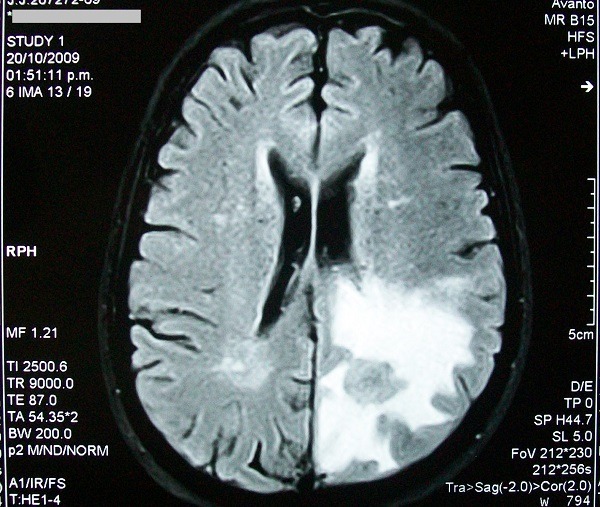

El edema cerebral

Se desarrolla en y alrededor del cerebro.